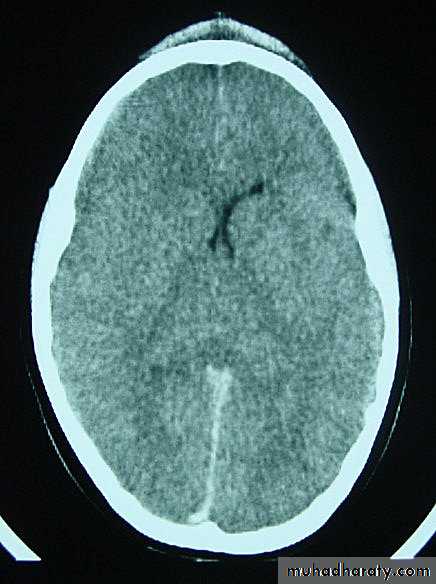

3. Brainstem and hemispheric (Cerebral) Contusion

These are areas of bruising and swellings with intact pia arachnoid, localized or generalized oedema and haemorrhage due to tearing of blood vessels.

3. Cerebral Contusion

Clinical presentations:

1. Prolonged periods of unconsciousness.

2. Focal neurological deficits that persist for longer than 24 hours.

CT scans demonstrates contusions as small areas of haemorrhage in the cerebral parenchyma.

Contusions may resolve with the accompanying deficits or they may persist.